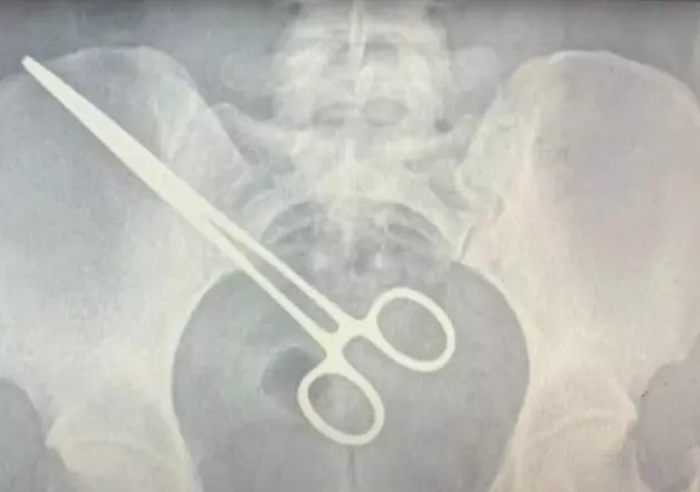

Foto: reprodução via SBT News

A imagem do raio-x mostra a pinça cirúrgica alojada no corpo da paciente. Com o objeto esquecido, uma nova cirurgia foi feita para a retirada do item, além de dez centímetros do intestino, ferido pela pinça. Por conta do erro médico, Jade procurou um advogado e pretende entrar com uma ação na Justiça.